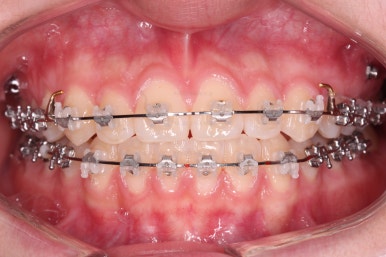

부산치아교정잘하는곳 키다리아저씨치과에서 치료를 시작한지 3개월째의 모습입니다.

솔직히 이정도만 해도 만족하시고 치료를 종료해달라는 분도 있긴 있어요.

하지만 교정치료를 시작한 이유가 앞니 가지런하게 하는 것도 있지만 왼쪽, 오른쪽 교합을 맞추는 것에도 있기 때문에 지금부터는 맞지 않는 교합에 초점을 두었어요.

추가로 사용한 장치는 바로 미니스크류(마이크로 임플란트) 장치입니다. 화살표를 보시면 잇몸뼈에다가 매우 작은 크기의 스크류를 식립해서 전체 치열을 밀고 당기고 해주는 거에요.

보시다시피 왼쪽 치열들의 교합이 뭔가 틈새가 많고 정확하지 않기 때문에 해당 부분에 미니스크류를 해서 교합을 맞춰주기로 했답니다.

아직 위아래 중앙선도 어긋나 있고, 교합도 아직은 미흡하네요.

계속 당겨주고 비대칭을 맞춰주고 하게 됩니다.